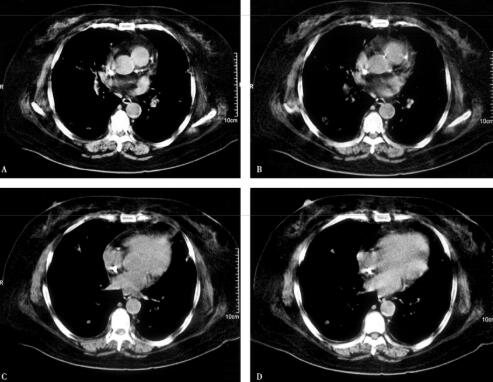

4.胸部CT:

双肺多发结节影、斑片影(图1肺窗,图2纵隔窗)。

图2

血气分析提示酸中毒及Ⅰ型呼吸衰竭,说明病情危重。血常规提示白细胞总数、中性粒细胞百分比均明显增高,说明感染重,结合患者因透析而留置颈内静脉导管,且导管周围皮肤红肿,现畏寒、高热,伴感染性休克等表现,综合分析,更加考虑是导管相关性败血症,进一步确诊需要血培养及导管尖端病菌培养的结果。目前病原学尚不明确,但是根据多年临床经验,糖尿病患者,免疫功能低下,易于感染金黄色葡萄球菌,并且该病菌在导管相关性血流感染的致病菌中占有重要地位,所以金黄色葡萄球菌致病的可能性大。这时胸部影像学提示双肺多发结节影、斑片影,这又是金黄色葡萄球菌感染的“经典”影像。所以目前考虑致病菌是金黄色葡萄球菌可能性极大。进一步的处理应是立即选择合适的抗感染药物进行治疗。